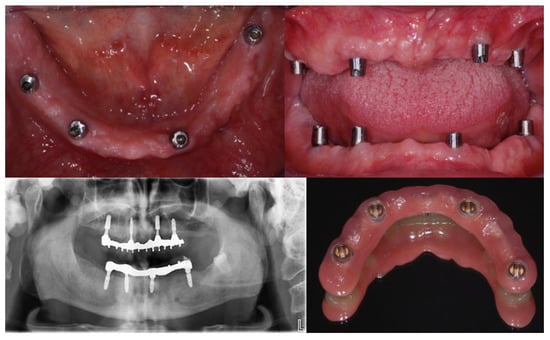

1. Introduction

2. Materials and Methods

2.2. Surgical and Prosthetic Procedures